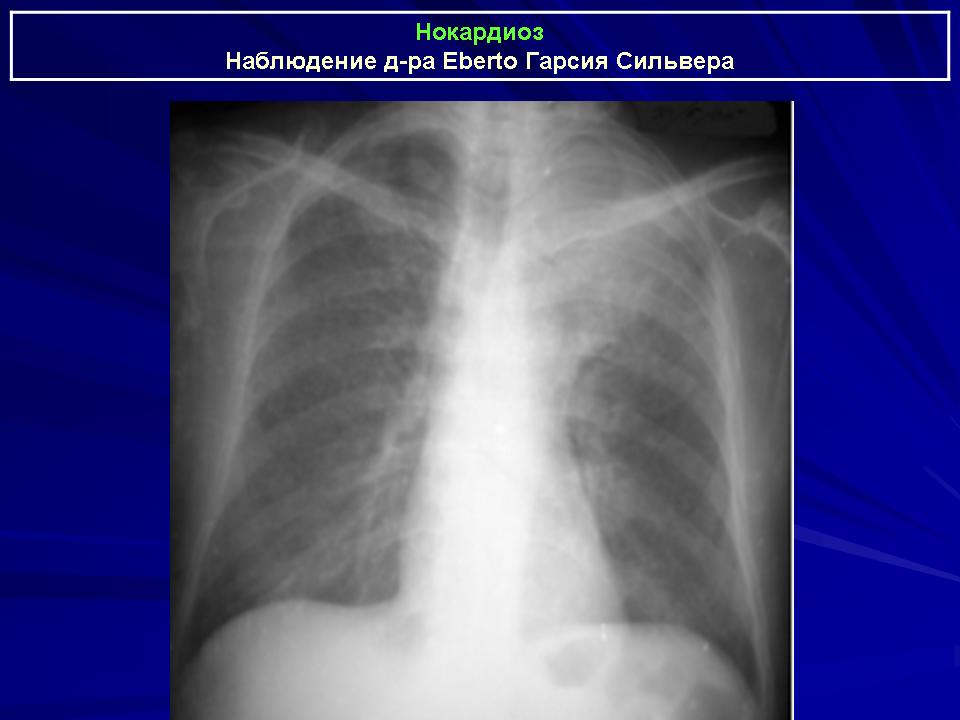

Нокардиоз

Нокардиоз (синонимы: стрептотрихоз, кладотрихоз, атипичный актиномикоз; Nocardiose - нем.; nocardiose - франц.) - микоз, характеризующийся длительным прогрессирующим течением с частым поражением легких, центральной нервной системы. Нередки летальные исходы.